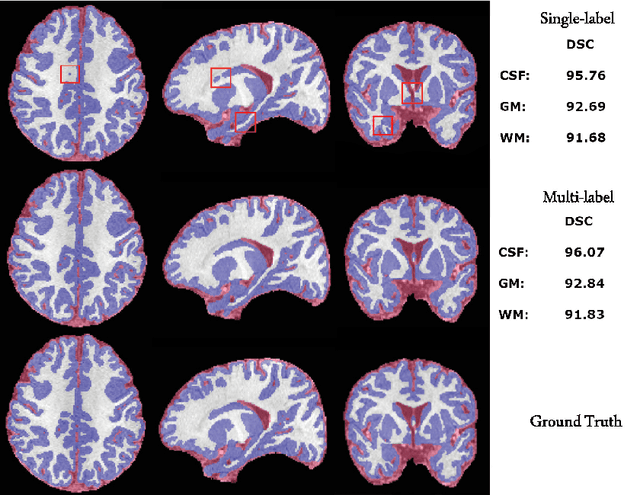

Abstract:The most recent fast and accurate image segmentation methods are built upon fully convolutional deep neural networks. Infant brain MRI tissue segmentation is a complex deep learning task, where the white matter and gray matter of the developing brain at about 6 months of age show similar T1 and T2 relaxation times, having similar intensity values on both T1 and T2-weighted MRIs. In this paper, we propose deep learning strategies to overcome the challenges of isointense infant brain MRI tissue segmentation. We introduce an exclusive multi-label training method to independently segment the mutually exclusive brain tissues with similarity loss function parameters that are balanced based on class prevalence. Using our training technique based on similarity loss functions and patch prediction fusion we decrease the number of parameters in the network, reduce the complexity of the training process focusing the attention on less number of tasks, while mitigating the effects of data imbalance between labels and inaccuracies near patch borders. By taking advantage of these strategies we were able to perform fast image segmentation, using a network with less parameters than many state-of-the-art networks, being image size independent overcoming issues such as 3D vs 2D training and large vs small patch size selection, while achieving the top performance in segmenting brain tissue among all methods in the 2017 iSeg challenge. We present a 3D FC-DenseNet architecture, an exclusive multilabel patchwise training technique with balanced similarity loss functions and a patch prediction fusion strategy that can be used on new classification and segmentation applications with two or more very similar classes. This strategy improves the training process by reducing its complexity while providing a trained model that works for any size input and is fast and more accurate than many state-of-the-art methods.